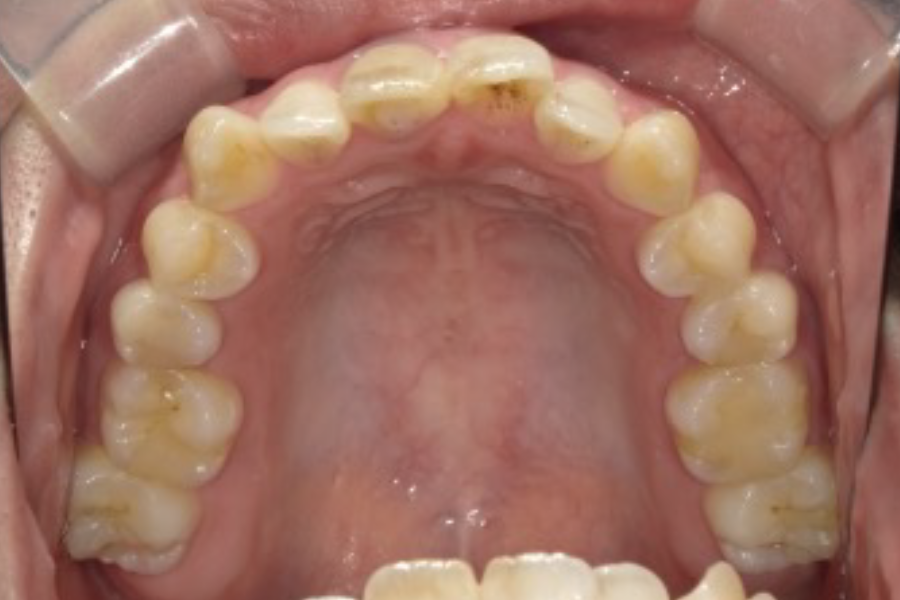

| 主訴 | 前歯の歯並びを綺麗にしたい |

|---|---|

| 診断名 | 叢生 |

| 年齢 | 20歳 |

| 治療期間 | 2年9ヶ月 |

| 治療費 | 基本料金 ¥880,000 調整料 ¥5,500/月 |

| 治療内容 | 上下顎左右側第一小臼歯抜歯 マルチブラケット装置(表側) |

| 治療のリスク | 装置の見た目、歯ブラシが難しい、疼痛、口内炎、歯肉退縮、歯根吸収 |